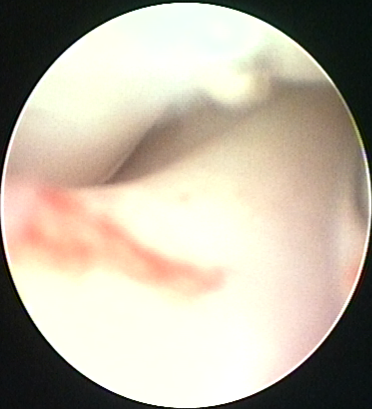

ARTROSCOPIA

Mediante l'utilizzo di ottiche di piccole dimensioni ,è possibile entrare dentro le singole articolazioni ,sia a scopo diagnostico, sia a scopo terapeutico.

Le articolazioni che sono più trattate sono : il gomito, per le patologie legate alla displasia del gomito, la spalla, per l'instabilità e le alterazioni osteocondrali, il ginocchio per le lesioni legamentose ,meniscali e artrosiche

L'artroscopia permette una valutazione efficace del gomito ed un trattamento di alcune componenti intra articolari con un rapido ritorno ad una completa funzione dell'arto.